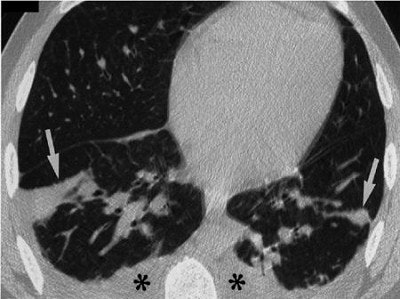

"Chest radiograph and CT scan showed patchy ground glass opacifications, thickening or respiratory airways, and bilateral pleural effusions," the authors wrote. A mineralogic analysis of the fluid from the patient’s bronchoalevolar lavage (BAL) identified 305 fibers per million alveolar macrophages. Other substances found in the patient’s lungs were fly ash, degraded glass, and amosite asbestos fibers.

| On this chest CT of the 38-year-old firefighter, patchy areas of consolidation (arrows) are depicted on a 1-mm thick section at the base of the lungs. The asterisks indicate bronchial wall thickening and small pleural effusions. Image courtesy of Dr. William Rom. |

A follow-up CT scan was performed 9 days after the firefighter was treated with corticosteroids. By then, the patients pulmonary function tests improved. The second CT scan showed near complete resolution. Another follow-up three weeks after discharge indicated the disappearance of the pleural effusions, Rom said.